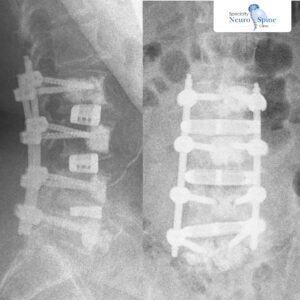

In 2022, Dr. Firas Husban became the first surgeon in the Middle East and North Africa (MENA) region to perform Oblique Lumbar Interbody Fusion (OLIF) surgery. Previously, OLIF – a groundbreaking minimally invasive spine procedure – was only accessible to patients overseas.

Unlike traditional open spine surgery, OLIF offers patients smaller incisions, reduced blood loss, shorter recovery times, and lower complication risks. Dr. Husban has since performed dozens of successful OLIF procedures with outstanding results — treating patients from adolescents to those in their 80s.